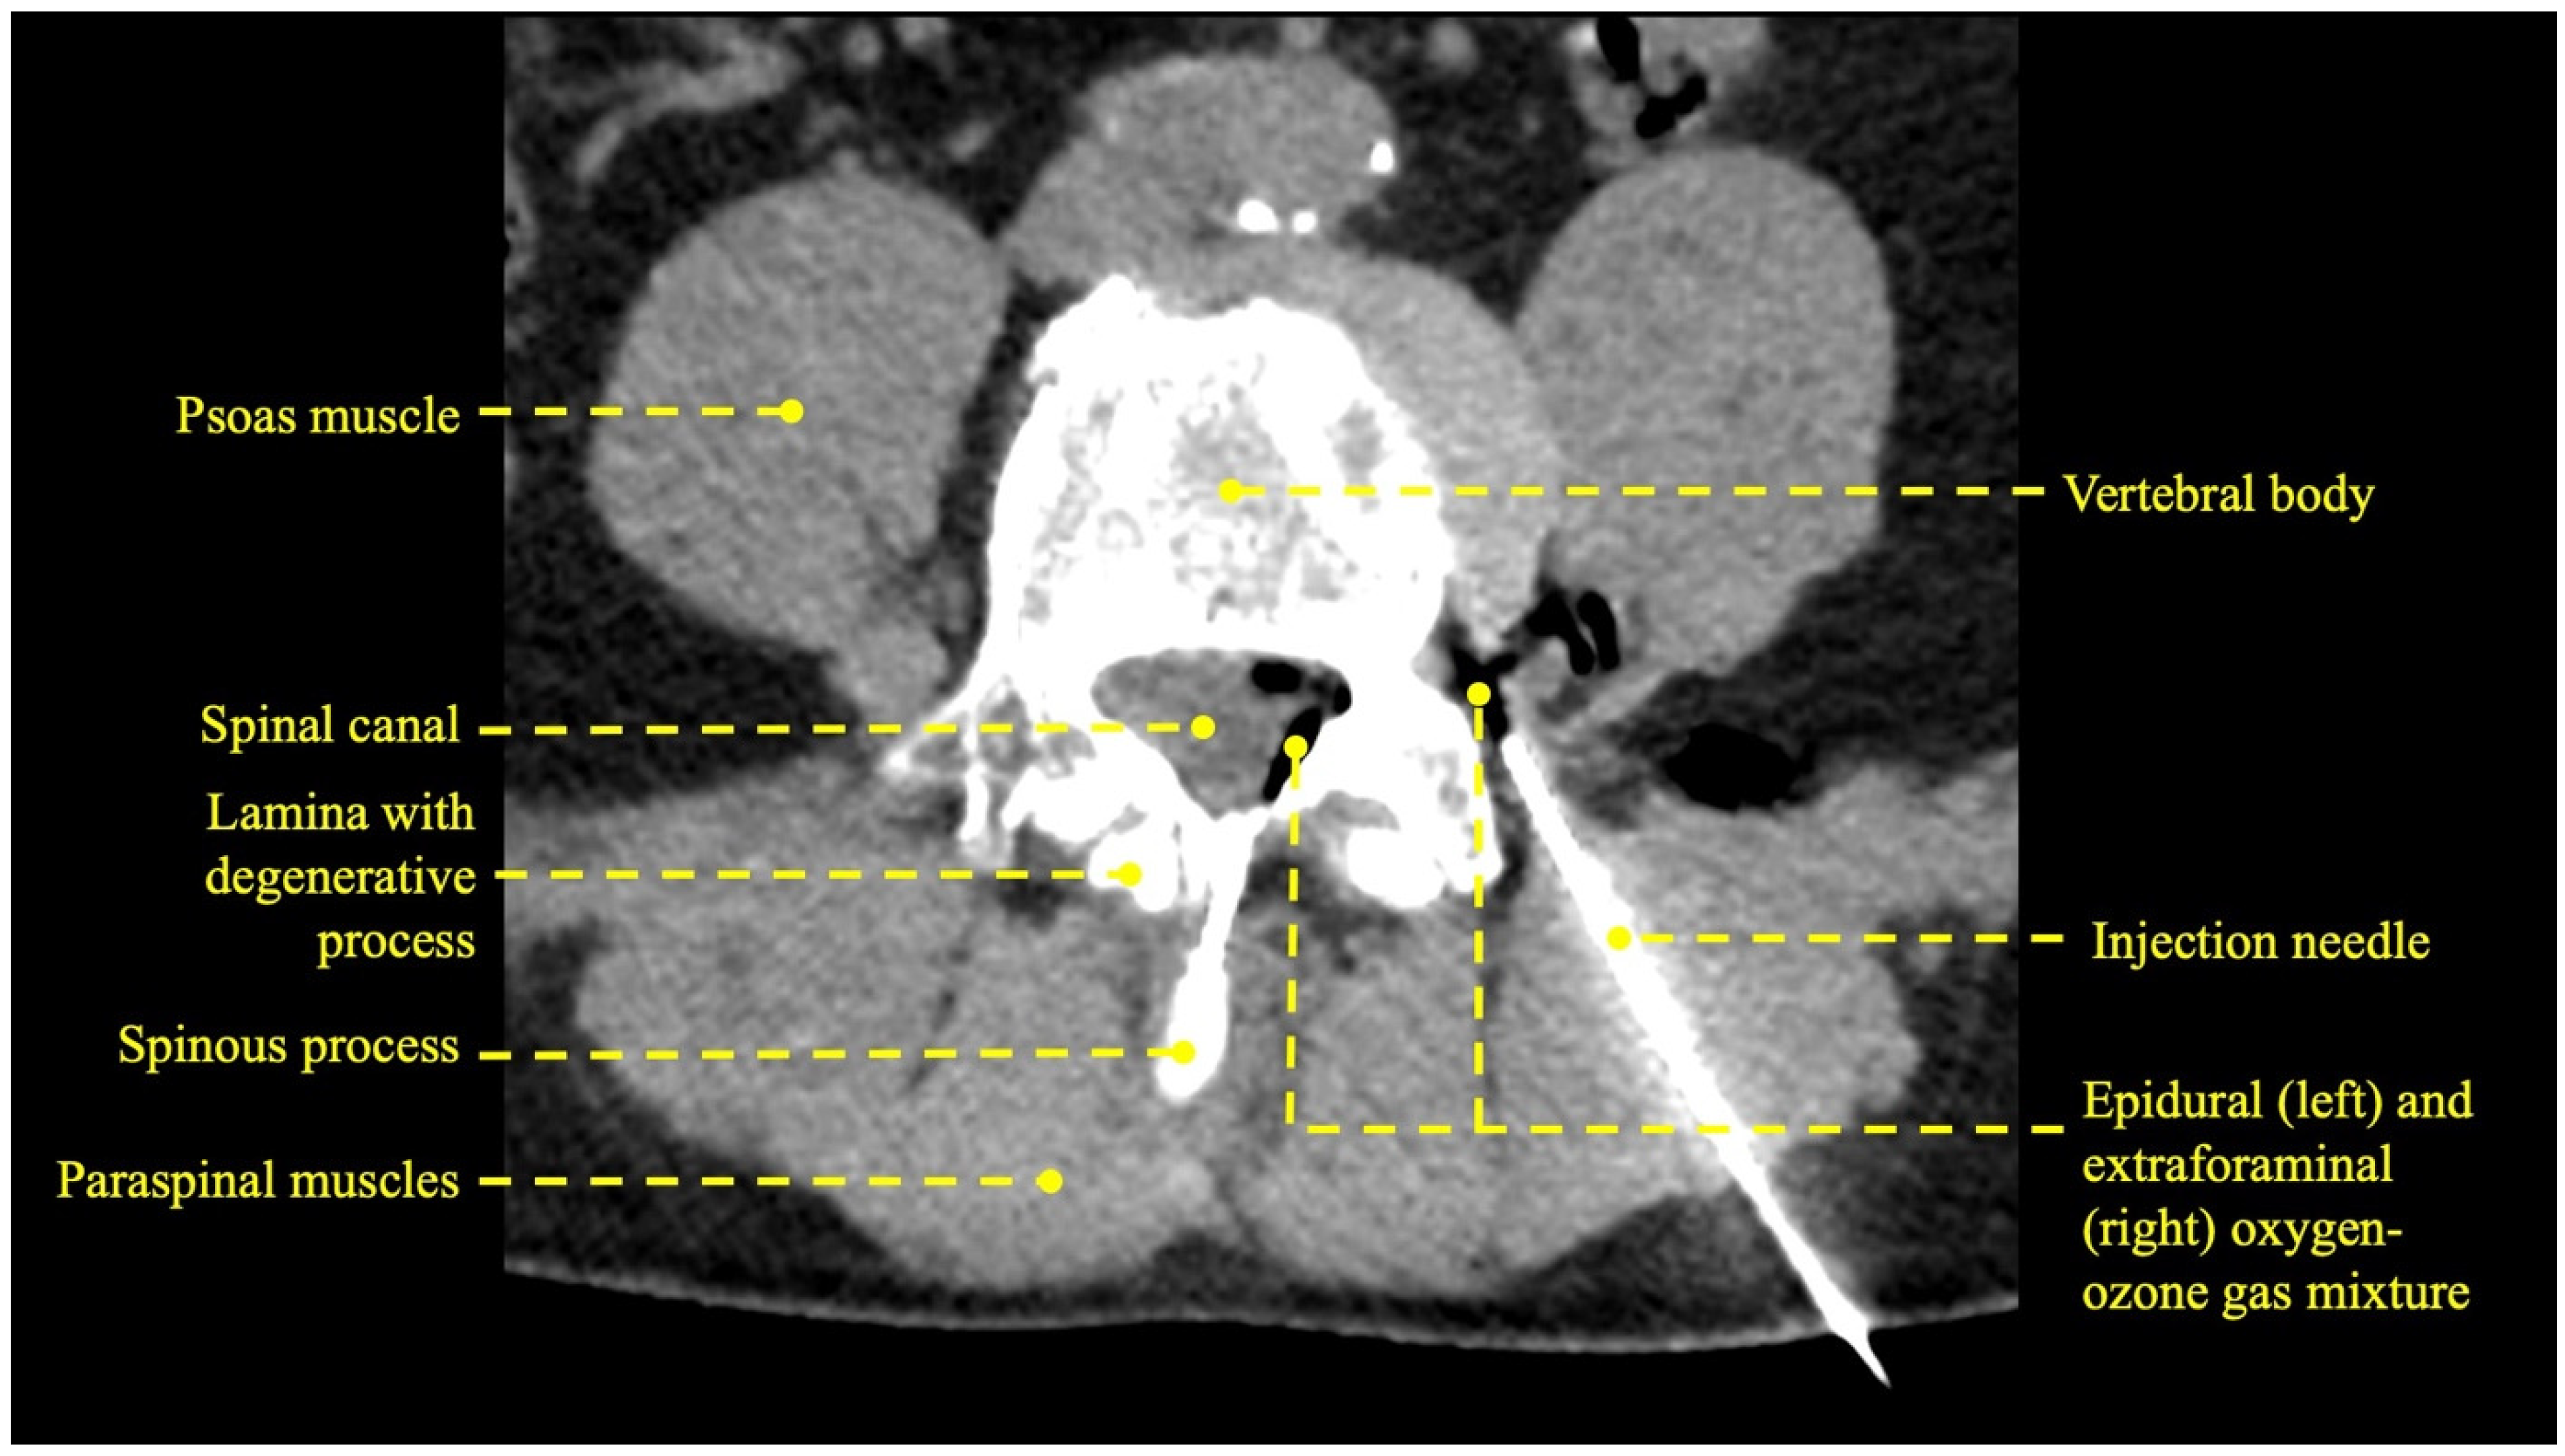

3.1. Procedural Technical Outcome

- Giurazza, F.; Guarnieri, G.; Murphy, K.J.; Muto, M. Intradiscal O2O3: Rationale, Injection Technique, Short- and Long-term Outcomes for the Treatment of Low Back Pain Due to Disc Herniation. Can. Assoc. Radiol. J. 2017, 68, 171–177. [Google Scholar] [CrossRef]